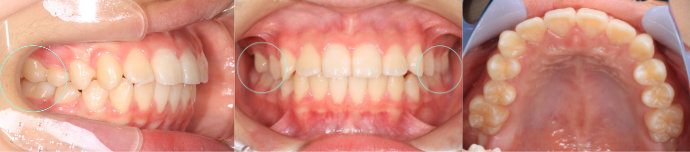

| Case11 |

| 受け口 および 右上の乳臼歯が早期に抜けたことにより、その後ろにある6歳臼歯が前方にずれている。そのため、6歳臼歯の直前にある永久歯が生える隙間がない。 |

| <治療前> |

|

| <治療後> |

| 主訴 |

前歯が反対になっている |

| 診断名 |

上顎右側第二乳臼歯の早期喪失による上顎右側第一大臼歯の近心転位、それに伴う上顎右側第二小臼歯の萌出スペース不足を伴う反対咬合

| 年齢 |

10歳 |

| 使用装置 |

マルチブラケット装置 |

| 抜歯部位 |

永久歯の抜歯は無し |

| 治療期間 |

3年8か月 |

| 治療費概算 |

検査・診断料:5万円+税 装置・技術料:25万円+税 来院ごとの処置・管理料:5,000円+税 保定装置料:5万円+税 |

| リスク・副作用 |

特になし |